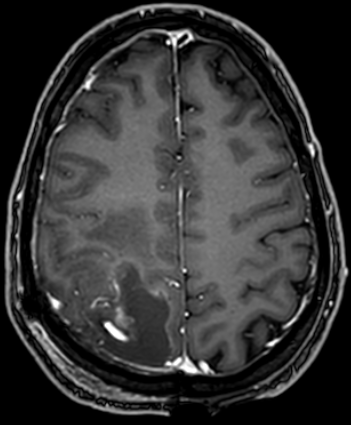

The first image is before surgery showing the tumor on the back side of the brain on the left.

The following picture is the result after surgery.